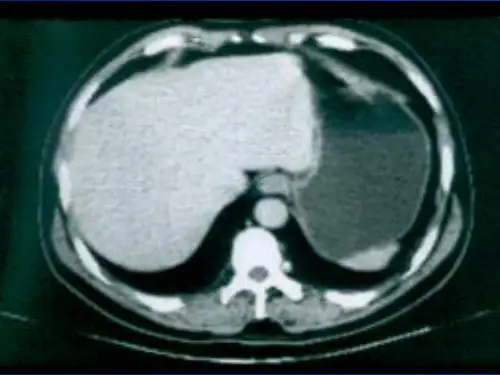

CT表現

• 肝臟形態輪廓的改變:肝邊緣凹凸不平,部 分肝段形態消失.

• 肝臟大小的改變:早期肝臟體積增大,中晚 期肝硬化肝葉增大和萎縮→肝葉比例失調.